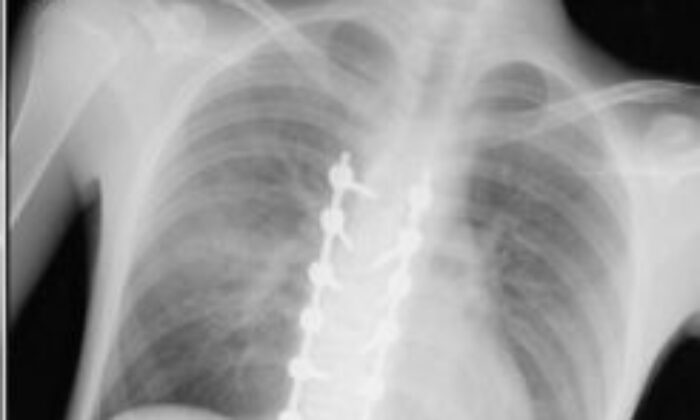

YUSUF GÜNDOĞMUŞ’UM VÜCUDUN TAKILAN PLATİNLER (BAHADIR TURGUT/ESKİŞEHİR-İHA)

“Beş gün entübe edildi. Ne olacağı belli değildi çıkmama ihtimali vardı. Şükürler olsun doktorlarımız ve Rabbim sayesinde entübeden çıktık. Hatta ciğerin birisinde infilak vardı; ciğer sorunumuzdan dolayı özellikle yoğun bakımda entübediydik. Beş günün sonunda ciğerleri toparlamaya başladı; entübeden çıkarttılar. Solunumu normale döndü. Sırayla sağlığı yerine gelmeye başladı. Bir hafta sonra kolundan ameliyat oldu platin koydular. Omurilikten ameliyat olduk. Omuriliğinde ilk röntgende tek kırık gördüler; üç kemiği birbirine bağlayacaklardı. Sonradan ikinci röntgende üç kırık olduğunu gördük; yedi kemiği birbirine bağladılar. Omuriliğe platin takıldı. 14 tane civatamız var. Şükürler olsun doktorlarımıza, Allah razı olsun. Evladımız gayet iyi, sağlıklı, yerinde. Artık işte suratta, çenede, burunda, elmacık kemiklerinde parçalı kırıklarımız var. Osman Gazi Fakültesi’nde Allah’ın izniyle buradaki hocalarımıza, önce Rabbim’e sonra hocalarımıza emanet çocuğumuz. İnşallah daha iyi olacağız; ben kendi adıma söylüyorum. Çocuğuma, her motora bindiklerinde sürekli kask ve montlarını giymelerini tembihliyordum. Giymediklerinde fırça atıyordum. Eskişehir’de birçok yerde tanınırız, tanırlar. Sevenimiz, eşimiz, dostumuz çok; uyarırlar, telefon gelir, haber verirler. Her duyduğumda, gördüğümde söylerim. Sağ olsun, çocuğum da o gün beni dinlemiş, kaskını takmış. Şükürler olsun ki takmış; takmasaydı o gün, o kazada belki çocuğumuzu kaybederdik